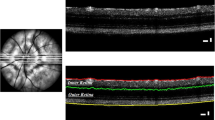

OCT imaging

Retinal structure was evaluated using OCT, which then allowed to perform the segmentation of retinal layers. In order to evaluate in vivo structural changes, a longitudinal study was carried out at 4, 8, 12 and 16 months of age using 3×Tg-AD and age-matched WT mice. In vivo OCT line and circular scans were acquired with Phoenix OCT2 together with Phoenix Micron IV retinal imaging microscope (Phoenix Research Laboratories, San Ramon, CA, USA). Retinal thickness was measured using InSight image segmentation software (v.1, Voxeleron LLC - Image analysis solutions, Chabot Drive, CA, USA) between the inner limiting membrane and the retinal pigment epithelium. For each eye, one OCT scan was performed around the optic nerve head and six scans were performed above and below the optic nerve head (Additional file 1: Figure S1A). Subsequently, measurements of ganglion cell layer (GCL) plus the inner plexiform layer (IPL), inner nuclear layer (INL) plus outer plexiform layer (OPL), outer nuclear layer (ONL), inner segments (IS) plus outer segments (OS) and total retina thickness were obtained both for 3×Tg-AD and WT animals (Additional file 1: Figure S1B). Circular and line scan thickness values for each animal are presented as the average value of both eyes. To perform OCT, animals were anesthetized using a combination of ketamine+xylazine 80 mg/kg + 5 mg/kg (Imalgene 1000, Merial, Lyon, France, and Rompum®, Bayer, Leverkusen, Germany, respectively) administered with one intraperitoneal injection. Pupils were dilated using topical tropicamide (1%, Tropicil®, Laboratório Edol, Carnaxide, Portugal). The cornea was anesthetized with topical anesthetic eye drops (4 mg/ml oxybuprocaine hydrochloride, Anestocil®, Laboratório Edol, Carnaxide, Portugal). The cornea was kept hydrated and optically cleared using hydroxypropyl methylcellulose (Methocel™ 2%, Dávi II Farmacêutica S.A., Barcarena, Portugal), during the whole procedure.

We evaluated, in vivo, whether the retinal structure of 3×Tg-AD mice was affected, using OCT (line and circle scans; Additional file 1: Figure S1), followed by the segmentation of retinal layers. ANOVA revealed that the total retina thickness was significantly decreased in 3×Tg-AD mice compared to that in WT mice (line scans, F (1, 33) = 100.2, p < 0.001; circle scans, F (1, 31) = 106.0, p < 0.001) (Fig. 1a, Additional file 1: Figure S3A). However, no time effect was observed (line scans, F (3, 99) = 1.3, p = 0.270) (Fig. 1a). Furthermore, throughout the study, we observed a significant thinning of GCL+IPL (F (2.6, 85.7) = 3.4, p < 0.05) and INL+OPL (F (2.2, 72.5) = 19.0, p < 0.001), whereas no time effect was observed on the IS+OS layer thickness (F (2.5, 82.8) = 0.73, p = 0.510). The thickness of each retinal layer was consistently significantly lower in 3×Tg-AD mice compared to WT mice (GCL+IPL, F (1, 33) = 121.8, p < 0.001; INL+OPL, F (1, 33) = 22.7, p < 0.001; IS+OS layer, F (1, 33) = 105.1, p < 0.001) (Fig. 1). Particularly, at 16 months, the total retinal thickness of WT mice, 192.3 μm, decreased to 177.9 μm in 3×Tg-AD mice (p < 0.001, Fig. 1a), and the thickness of GGL+IPL decreased from 60.7 μm in WT mice to 51.0 μm in 3×Tg-AD mice (p < 0.001, Fig. 1b), whereas the IS+OS layer thickness was 39.5 μm and 33.1 μm in WT and 3×Tg-AD mice, respectively (p < 0.001, Fig. 1e). However, conversely to the results obtained for the layers described above, a significant increase of ONL thickness (F (2.6, 85.1) = 8.6, p < 0.001) was observed, during the study. Also the thickness of ONL of 3×Tg-AD mice was significantly higher (F (1, 33) = 8.7, p < 0.01) in comparison with WT mice (Fig. 1d). At 16 months, the ONL thickness was 58.8 μm and 55.5 μm in 3×Tg-AD and WT mice, respectively (p < 0.001). Overall, we observed a thinning of total retina, GCL+IPL, INL+OPL, and IS+OS of 3×Tg-AD mice. Conversely, ONL was found to be thicker in this AD animal model.

Thickness of different retinal layers in WT (white bars) and 3×Tg-AD (black bars) mice at 4, 8, 12, and 16 months of age, based on in vivo OCT line scans. The thickness of retinal layers was measured using the InSight software. a Total retina, b GCL+IPL, c INL+OPL, d ONL, e IS+OS. The results are presented as mean ± SEM. *p < 0.05, ***p < 0.001, according to Student’s t test. nWT: at 4 months = 21, at 8 months = 19, at 12 months = 17, at 16 months = 17; n 3×Tg-AD: at 4 months = 22, at 8 months = 22, at 12 months = 22, at 16 months = 22